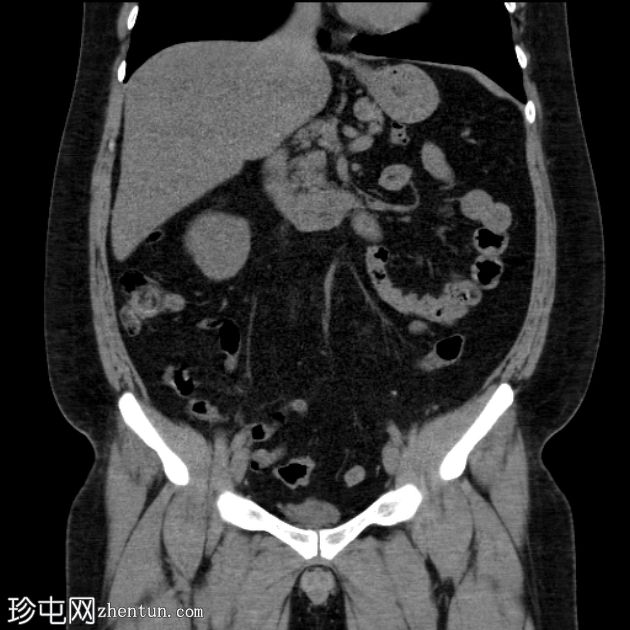

CT扫描

冠状位

平扫

肝下阑尾,无急性炎症改变。

左肾切除史。

未见右肾、输尿管或膀胱结石。无反压改变。

肝下阑尾是一种罕见的解剖变异,阑尾位于肝脏下方,通常是由于胚胎发育过程中肠旋转不全所致。

肝下阑尾炎是指阑尾和盲肠位于“肝下”位置时发生的炎症,如本例所示。

肝下阑尾炎在临床上常与肝胆疾病相似。